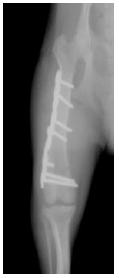

2. 中型犬の太ももの骨折(大腿骨骨折)

治療2ヵ月後のレントゲン写真です。 折れた骨が正常な位置でしっかり固定されているのが確認出来ます。 治療後、この子は痛みも無く元気に走り回っています。 |